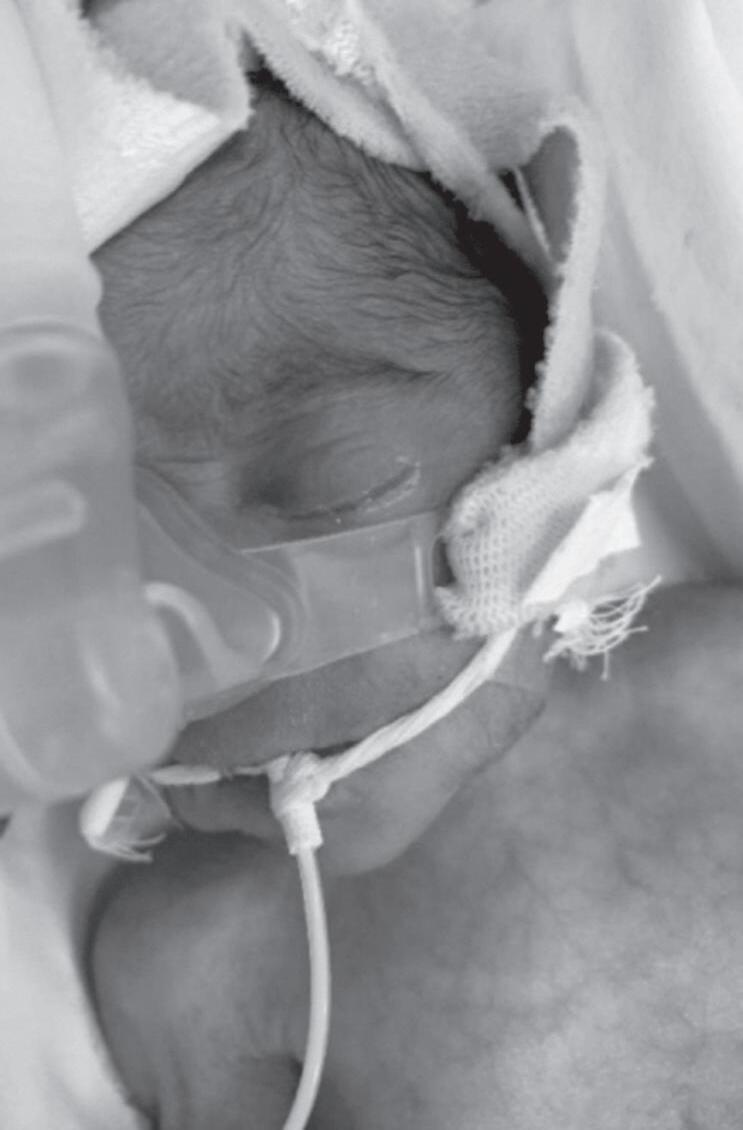

Aumento de bilirrubina direta e transaminases

Função renal pode ser acometida e alterações sugestivas de doenças oportunistas associadas

LCR: líquido cefalorraquidiano; VDRL: Estudo Laboratorial de Doenças Venéreas (do inglês Venereal Disease Research Laboratory); HIV: vírus de imunodeficiência humana.

Fonte: elaborada pelo autor.

ALTERAÇÕES DE